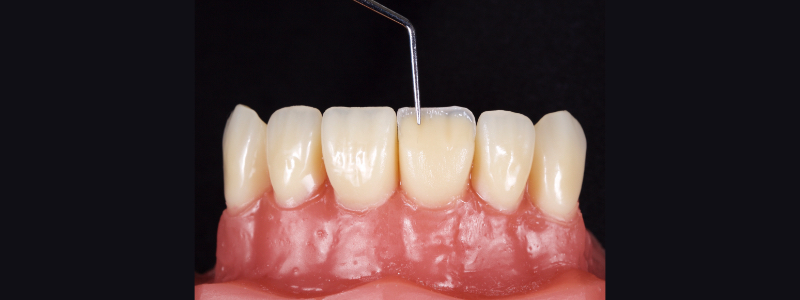

Before polymerization, the contact points are cleared with an Interproximal Carver Long (IPCL) like American Eagle (Fig. 9). The resin mass is then polymerized to create a palatal shell (Fig. 10).